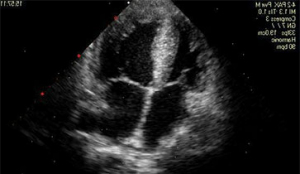

L’ecocardiogramma è una tecnica che si basa sull’impiego di ultrasuoni e consente di vedere dall’interno sia le pareti del cuore sia le sue strutture interne (come le valvole) e di valutare esattamente la contrattilità del cuore globale.